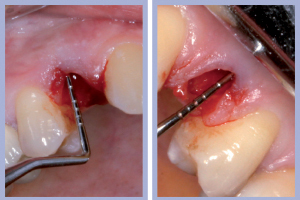

- Figg. 4a, b – Scollamento

- Figg. 5a, b – Estrazione dei canini da latte

- Figg. 6a, b – Estrazione dei canini da latte

- Figg. 7a, b – Toilette chirurgica

- Figg. 8a, b – Mappatura alveolare tramite sonda parodontale

– Estrazione minimamente traumatica degli elementi dentali (Figg. 4-6);

– Sondaggio alveolare e revisione chirurgica (Figg. 7-8);